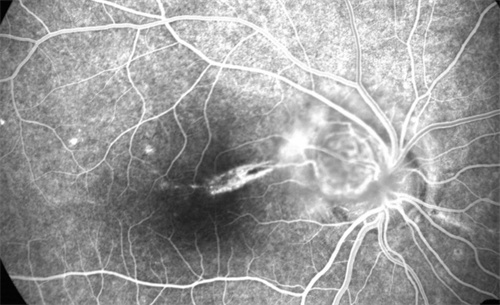

术前,患者需接受超全眼科检查,包括视力测试、眼底检查和OCT扫描,以评估病情并制定手术方案。

首可靠行玻璃体切除,清除眼内玻璃体以提供清晰视野;随后使用特定染色剂(如亮蓝)使黄斑前膜显色,便于比较准操作。

在显微镜下,医生用精细工具(如视网膜钩或镊子)小心抓住并剥离前膜,尽量减少对视网膜的损伤。

剥除后,详细检查视网膜表面是否有残留膜,并清理干净。然后,向眼内注入平衡盐溶液维持眼球形状,闭合切口。